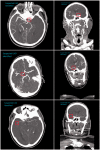

Rapid and accurate diagnosis of large vessel occlusions (LVOs) in acute ischemic stroke (AIS) patients using automated software could improve clinical workflow in determining thrombectomy in eligible patients. Artificial intelligence-based methods could accomplish this; however, their performance in various clinical scenarios, relative to clinical experts, must be thoroughly investigated. We aimed to assess the ability of Canon's AUTOStroke Solution LVO application in properly detecting and locating LVOs in AIS patients. Data from 202 LVO and 101 non-LVO AIS patients who presented with stroke-like symptoms between March 2019 and February 2020 were collected retrospectively. LVO patients had either an internal carotid artery (ICA) (n = 59), M1 middle cerebral artery (MCA) (n = 82) or M2 MCA (n = 61) occlusion. Computed tomography angiography (CTA) scans from each patient were pushed to the automation platform and analyzed. The algorithm's ability to detect LVOs was assessed using accuracy, sensitivity and Matthews correlation coefficients (MCCs) for each occlusion type. The following results were calculated for each occlusion type in the study (accuracy, sensitivity, MCC): ICA = (0.95, 0.90, 0.89), M1 MCA = (0.89, 0.77, 0.78) and M2 MCA = (0.80, 0.51, 0.59). For the non-LVO cohort, 98% (99/101) of cases were correctly predicted as LVO negative. Processing time for each case was 69.8 ± 1.1 seconds (95% confidence interval). Canon's AUTOStroke Solution LVO application was able to accurately identify ICA and M1 MCA occlusions in addition to almost perfectly assessing when an LVO was not present. M2 MCA occlusion detection needs further improvement based on the sensitivity results displayed by the LVO detection algorithm.